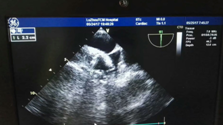

近日, 我院专家团队通力配合,成功为一名78岁高龄的患者实施了左心耳封堵术。专家在患者左心耳置入了一个封堵器,从而有效地预防了患者发生房颤卒中的风险,据悉,这是川南地区成功开展的首例经食道超声指引下的“左心耳封堵术”。 手术中 78岁高龄老人房颤致血栓 服药无效 江阳区一...